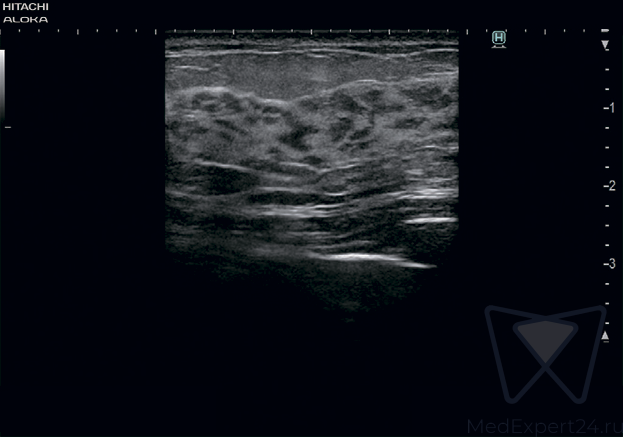

Hitachi-Aloka Lisendo 880 система УЗИ для проведения сложный кардиоваскулярных исследований. В системе доступна 2D/4D визуализация, есть аналитика и современные функции. Это новейшая система для диагностики в клинических условиях.

Сканер поддерживает работу новых поколений датчиков - CMUT и монокристаллических.

- Выдающееся ультразвуковое изображение высокого разрешения благодаря новым датчикам, фокусировке по всей глубине исследования и OLED монитору.